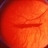

- subhyaloid hemorrhage, HRC-PDR

- Fundus camera

- Boat shaped subyaloid hemorrhage due to underlying NVE in a patient with HRC-PDR.